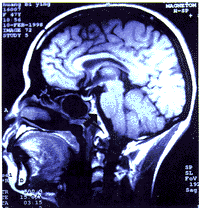

2.1 颅底骨受累的部位:全组128例患者中,97例有颅底骨受累(经反复阅片),占75.8%(97/128), 其发生部位以斜坡最为常见,占81.4%(79/97), 其次为蝶骨46.4%(45/97)、岩骨44.3%(43/97),单一部位仅占24.7%(24/97)。破坏斜坡脑面出现硬脑膜强化增厚者21例占16.4%(21/128),其中头痛者19例占90.5%(19/21),颅神经阳性者17例占81.0%(17/21), 6例放射治疗后0~14个月再行MRI检查的患者, 强化增厚的硬脑膜全部恢复正常或明显变薄(见图1)。

a 放射治疗前斜坡脑面硬脑膜明显变厚(黑箭头所指)

b 放射治疗后全部恢复正常

图1 放射治疗前、后的颅MRI片